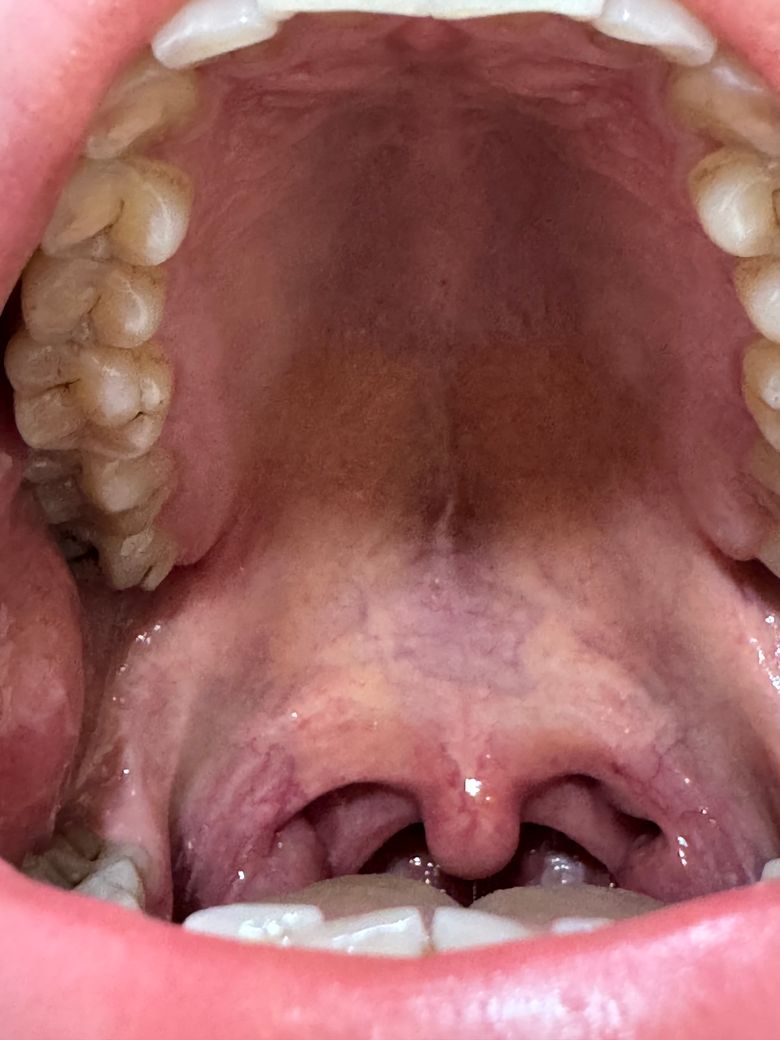

입천장에 하얀색같은게있는데요….

입천장 가운데가 햐얗게 되어있는데

원래 이런건지

아니면은 병원을 가봐야하는지

통증은 전혀없습니다.

• 1번 째 사진

사람마다 조직의 형태는 다를 수 있습니다. 염증 등의 소견은 없어보이며 걱정할 건 아닌 것 같습니다.

입천장이 뜨거운거나 자극적인 음식등에 화상을 입은거 같습니다. 큰문제가 잇는건 아니니 당분간 자극이 가지 않도록 해주시는게 좋습니다.

사진으로는 정확한 확인이 어려워 보입니다. 입찬장에는 오톨도톨한 돌기가 있는데 이런 부분들이 하얗게 보이는 할 수 있습니다.

대부분 큰 문제가 되는 것은 아니기 때문에 너무 걱정하지 않으셔도 될 것으로 생각됩니다. 자세한 확인을 위해서 치과에서 진료를 받아보는 것을 권유드립니다.

입천장 형성과정에서 양쪽 입천장이 가운데쪽으로 자라면서 서로 근접하면 유합되게 됩니다. 그 유합선의 흔적이고 특별히 이상한 점은 없는 것 같습니다.